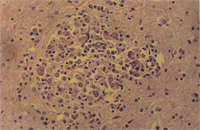

肉眼病變: 局部性慢性炎症見於整個腦組織,主要侵犯血管周圍形成很厚的非化膿性炎症細胞增生(圖1),包括淋巴球、組織球、類上皮細胞、吞噬細胞與少許漿細胞,偶爾亦有嗜中性球(圖2)。炎症細胞圍繞血管厚薄不一,圍繞不均勻,有時較集中於血管一端而呈偏心。又各種炎症細胞出現增生程度不均,有的圍繞為清一色淋巴球(圖3),有的則大部分為組織球或吞噬細胞(圖4)。特殊染色如PAS並無特殊發現,本病例又可看到一些血管變性(degenerated vessels)。病變發生於腦脊髓與腦膜,灰白質均可被侵犯,炎症細胞增生,侵犯非只限於血管周圍,亦可侵入腦實質neuropil。